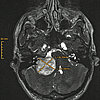

Eine MRT-Aufnahme des Kopfes auf dem ein Akustikusneurinom in der linken Kopfhälfte zu sehen ist.

Die MRT-Aufnahme zeigt ein Akustikusneurinom als kontrastmittelaufnehmende Raumforderung in der Nähe der Ohrregion.